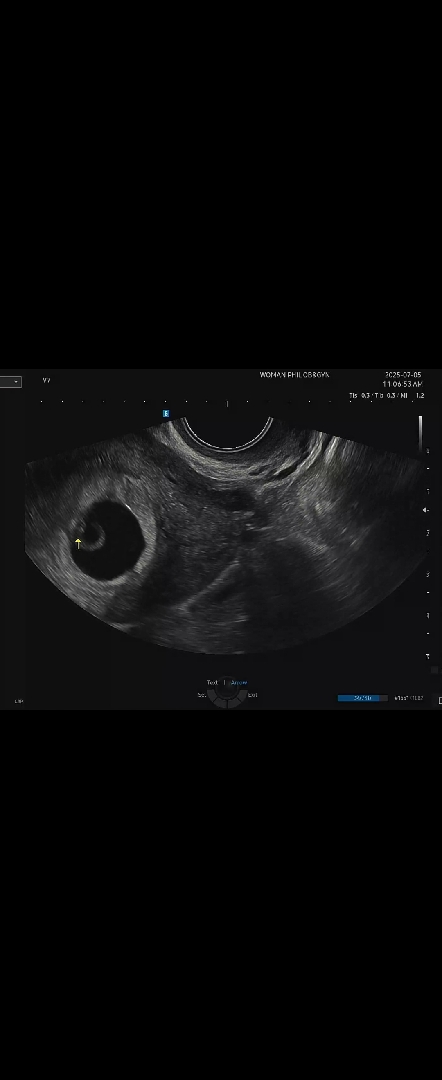

7주입성..애기심장소리가 안들린데요...

애기 심장소리를 들을 수 있을거란 기대 가지고 갔는데... 애기는 아주 작지만 심장이 뛰지 않는데요 일단 월요일 다시 확인해서 심장이 뛰지 않는다면 유산 진단된다는데 이러한 일이 흔한가요... 눈물밖에 나오지 않네요.. 다 제 잘못같아요 심장뛰는걸 늦게 확인 하는 경우도 있을까요... 너무 속상하네요